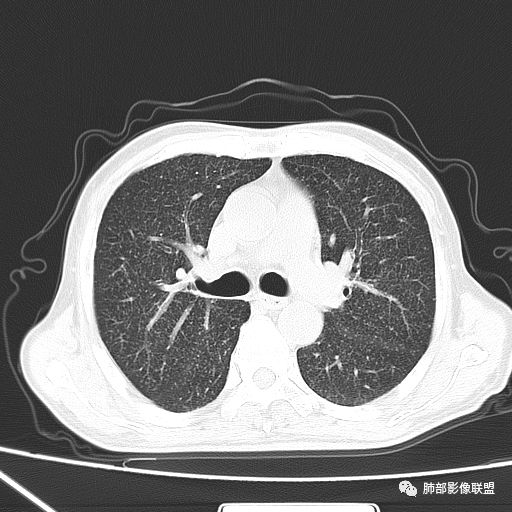

2019-10-20复查CT如下:

两肺弥漫性粟粒样结节伴左上肺小结节,呈三均匀分布,有结核的临床表现,支持血性播散性肺结核。

大小、分布均匀,边缘清楚

细小结节,弥漫,撒米粒样——血道来源

血道来源的病灶,均匀、细微,而且部分有分支状,都符合粟粒型肺结核

急性血行播散型肺结核  两肺广泛分布粟粒大小的结节状密度增高影,具有大小均匀、分布均匀、密度均匀的典型“三均匀”特征,注意急性血播病灶非常小,一般粟粒影直径1~2mm。

病灶密集者出现肺外围血管影不清或减少。